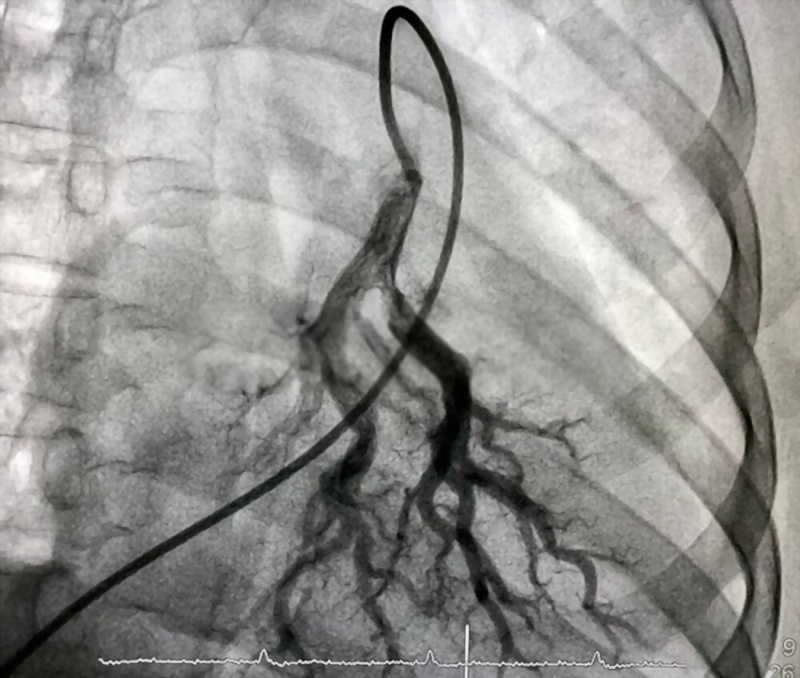

Chụp động mạch phổi là kỹ thuật chính xác nhất để chẩn đoán bệnh thuyên tắc phổi cấpChụp động mạch phổi thể hiện hình ảnh rõ nét về lưu lượng máu trong các động mạch ở phổi của người bệnh. Chính vì vậy, đây là kỹ thuật chính xác nhất để chẩn đoán bệnh thuyên tắc phổi cấp. Tuy nhiên, khi thực hiện kỹ thuật này đòi hỏi kỹ thuật viên có tay nghề cao và kỹ thuật này cũng có một số nguy cơ nguy hiểm. Vì vậy nên, chụp động mạch phổi chỉ được thực hiện khi các kỹ thuật chẩn đoán khác không thể cung cấp đầy đủ thông tin để chẩn đoán chính xác là thuyên tắc phổi hay là không.